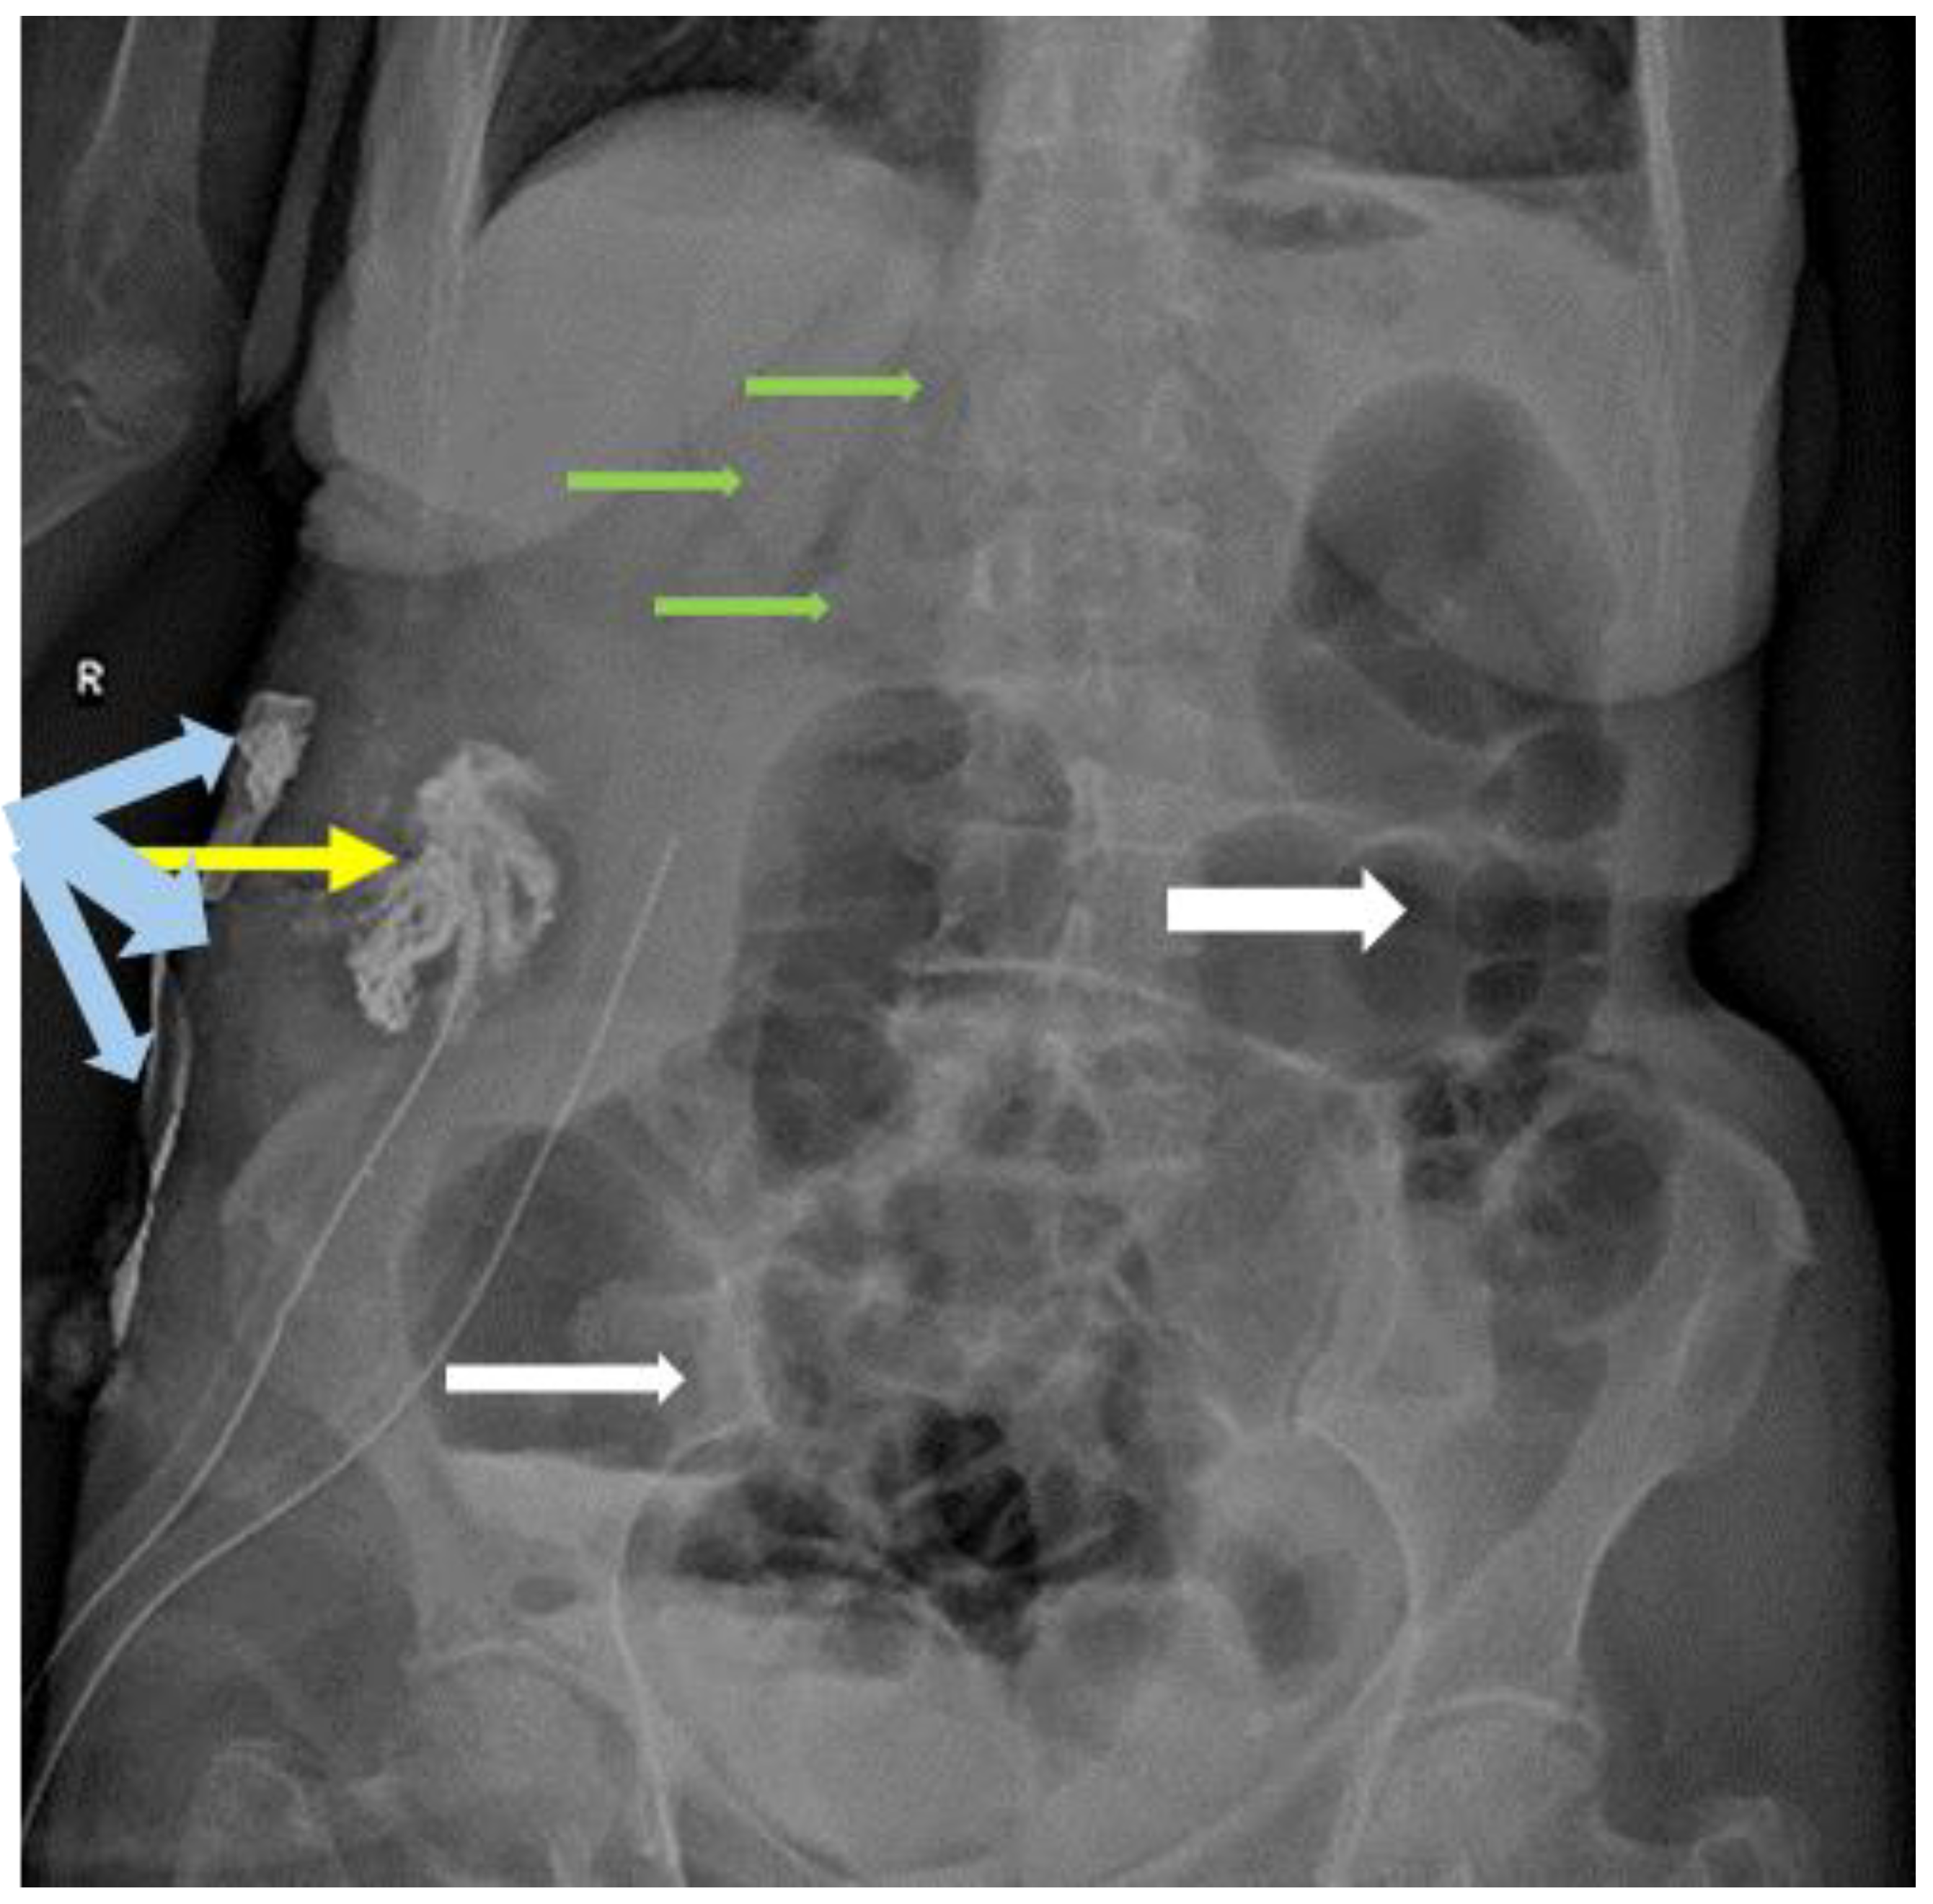

Abdominal X-ray with injection of water-soluble contrast through the abscess drain was used on postoperative day 3, to evaluate the size of the abscess cavity (Figure 3); intrahepatic pneumobilia was still visible, without any evident communication with the CBD.

Figure 3. Abdominal X-ray showing aerocolia (white arrows); pneumobilia (green arrows); abscess cavity containing Iodoform-impregnated gauze (yellow arrow).